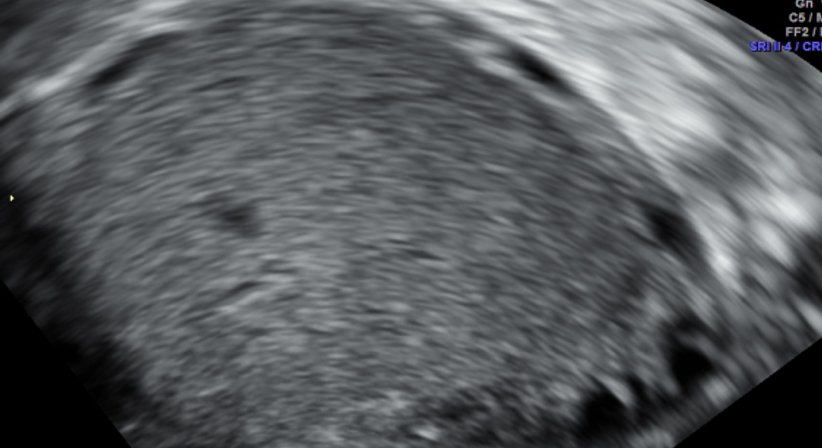

Zysten:

Zysten im Bereich der Eierstöcke sind grundsätzlich etwas sehr häufiges. Die meisten sind so genannte funktionelle Zysten, die durch Retention von Follikeln entstehen und üblicherweise nach einer oder zwei Menstruationsblutungen wieder verschwinden. Solche Zysten findet man nach der Menopause nicht mehr! Funktionelle Zysten sind eigentlich nicht weiter gefährlich, es sei denn, wenn sie an Größe zu stark zunehmen. Wenn dies geschieht, können sie durch die so genannte Stieldrehung (ähnlich wie bei einem geknickten Gartenschlauch) zu einem sehr akuten Bauchschmerz führen, der die sofortige Einlieferung in eine Krankenhaus erfordert.

Die Beurteilung von Eierstockzysten erfolgt üblicherweise durch ein geeignetes, hochwertiges Ultraschallgerät, da auch die Blutversorgung mittels Farbdoppler-Technik wichtig für die Differentialdiagnose ist.